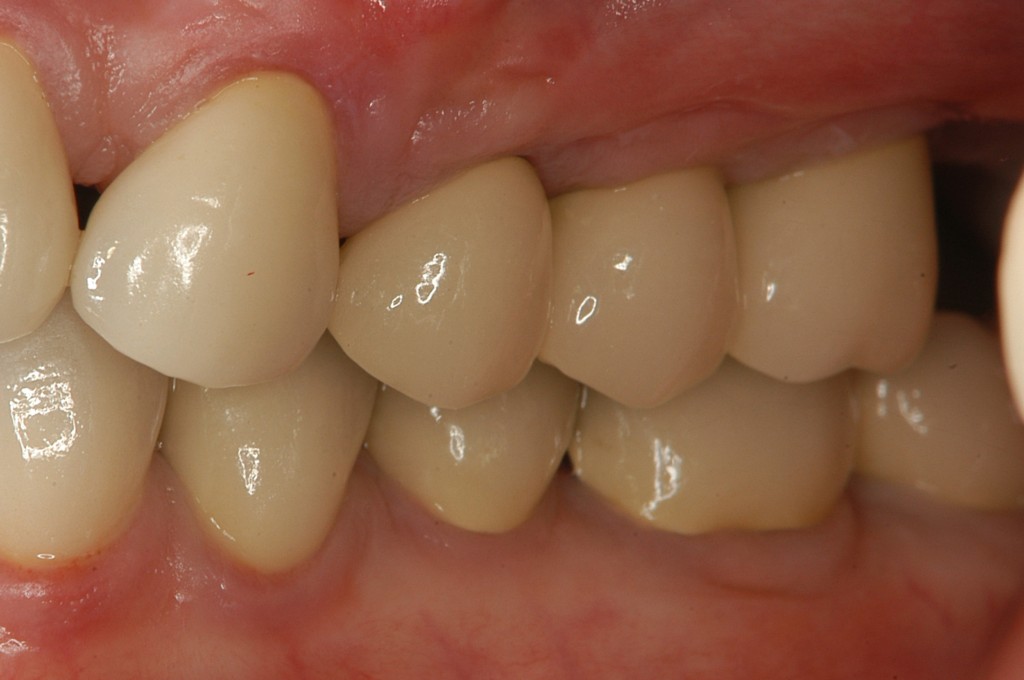

インプラントを埋入し,セラミックスクラウンを被せました。

奥歯でも食べ物を噛めるようになり,大変満足していただきました。

治療後のレントゲン写真です。長さ,太さの十分なインプラントが再生した骨によって支えられているのが分かります。